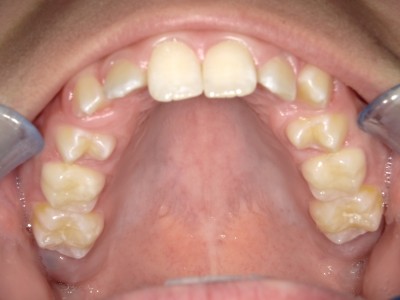

Retentie: Wrap + C-C bar onderkaak